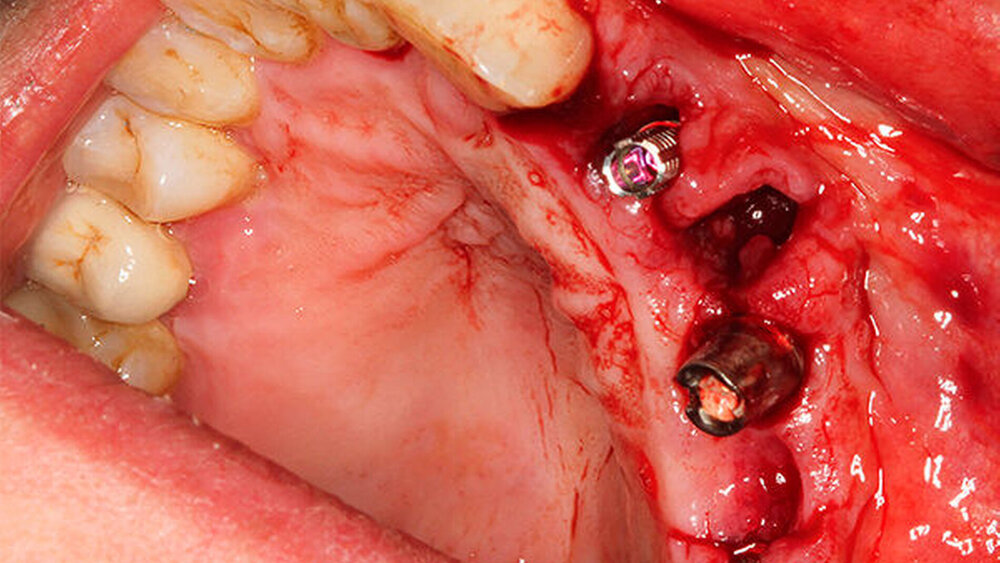

Schnutenhaus:

Wir haben extrahiert, dann die Implantate inseriert, direkt nach der Implantation die Scanbodys aufgesetzt, den optischen Abdruck genommen und das Langzeitprovisorium aus PMMA verschraubt. Dass die Innenverbindung immer die gleiche ist, hilft dabei sehr. Eine Prothetik passt tatsächlich auf alle Implantate.